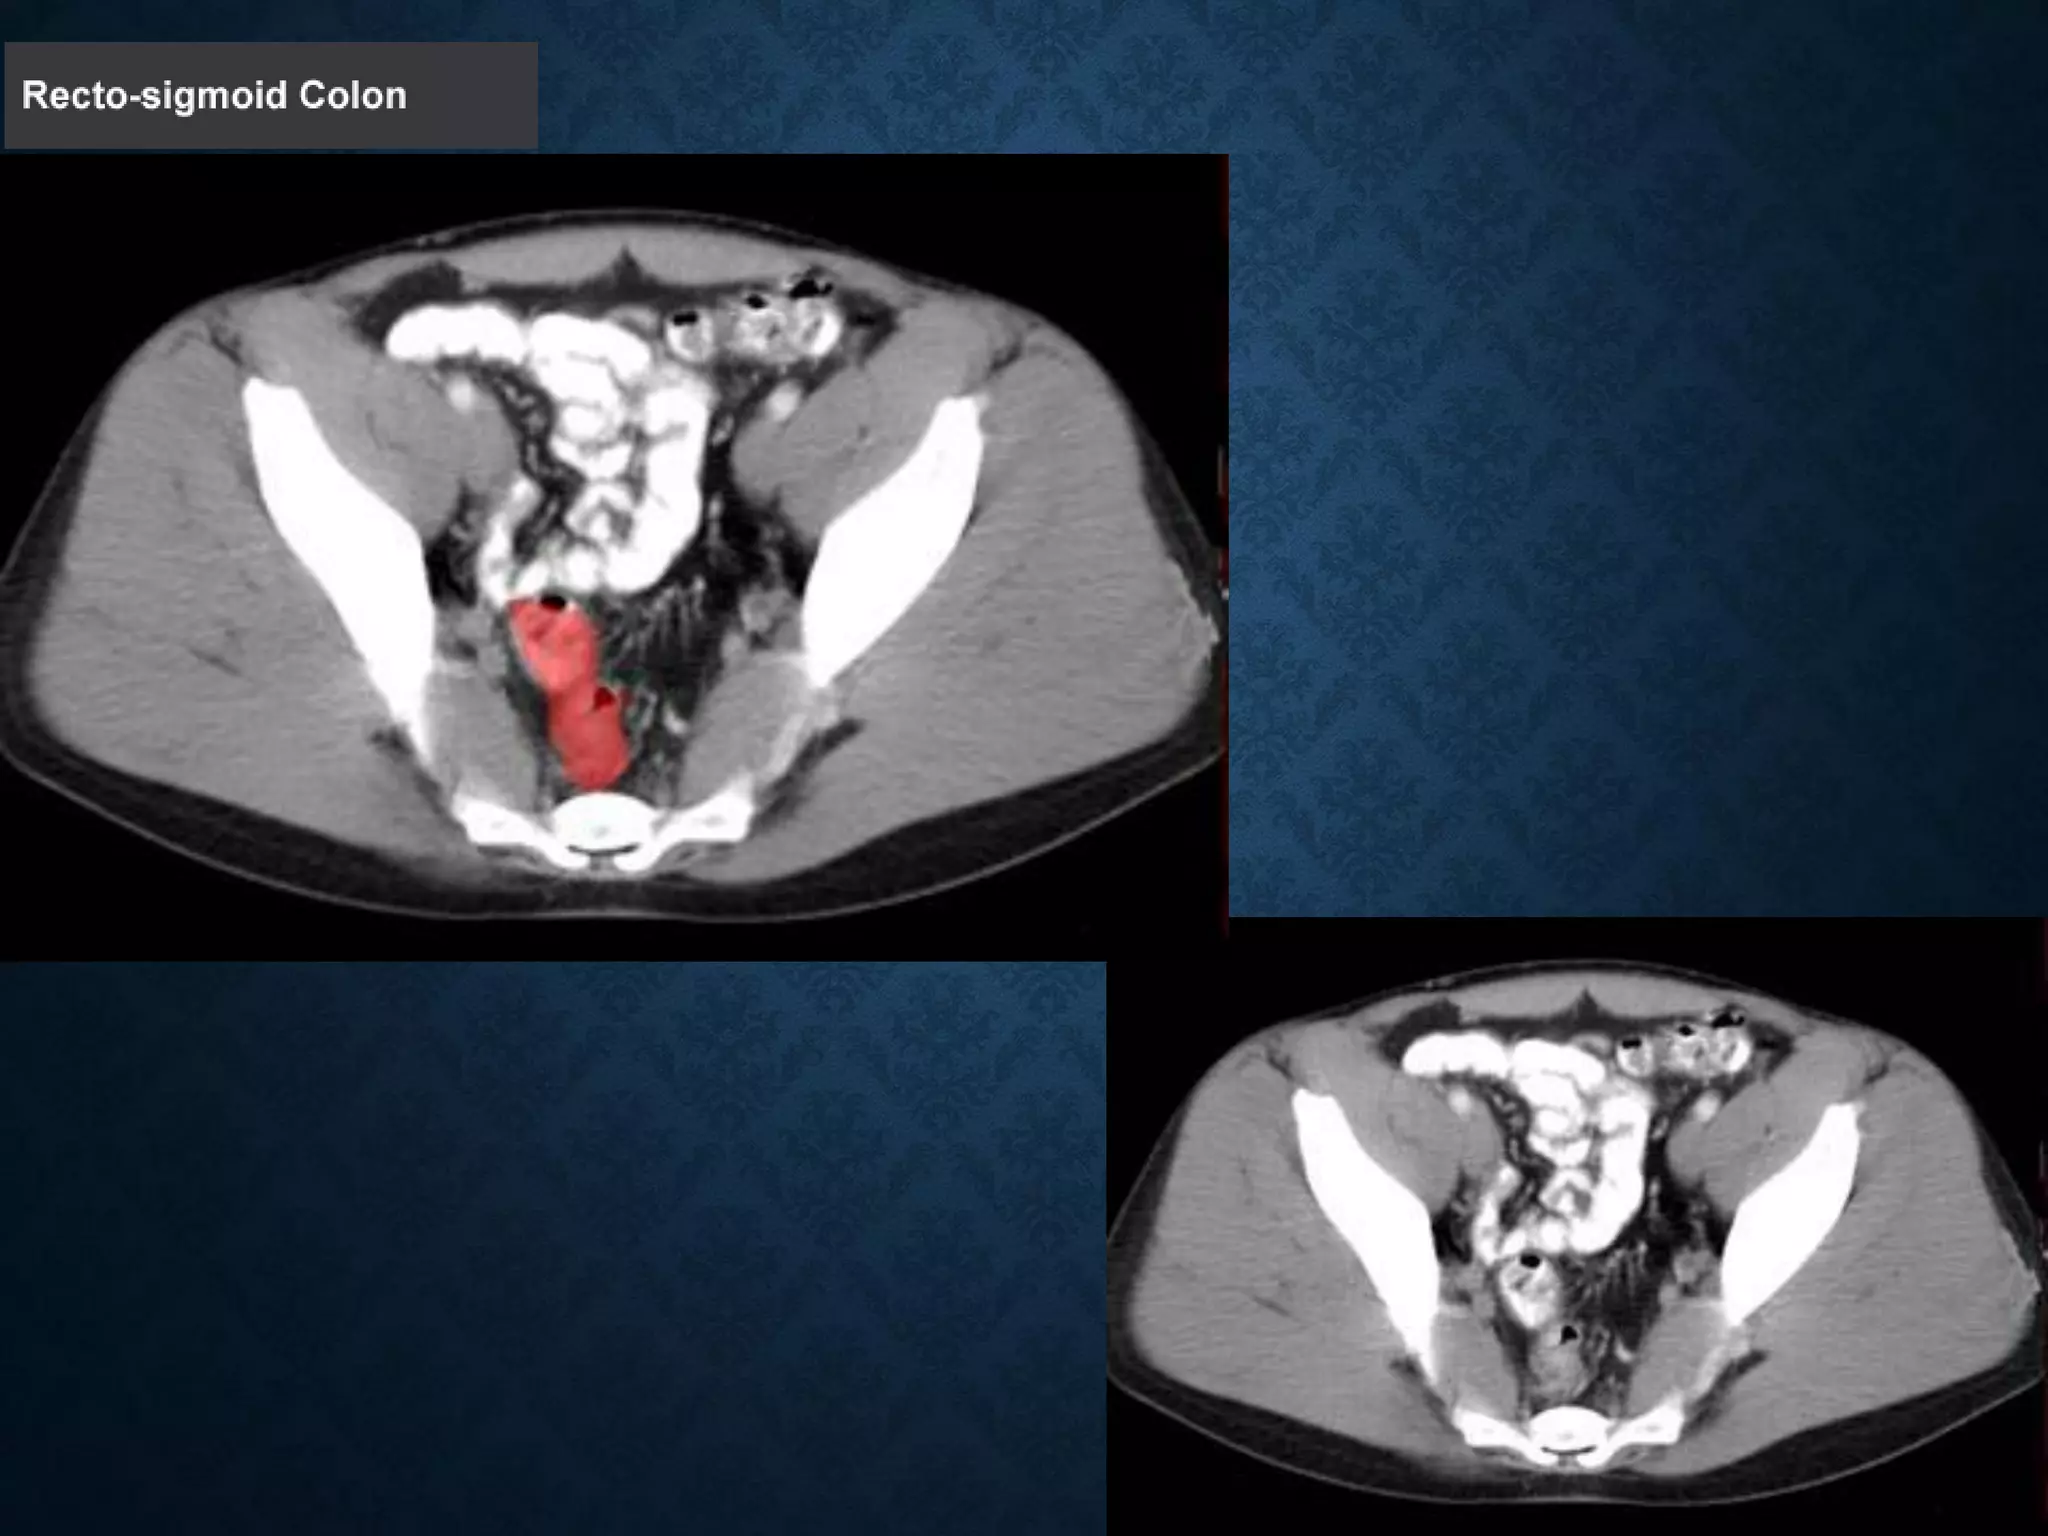

Identify the following structures in the body CT to the right. To view the location of the structure in the image click on

the label at the left and the structure will be indicated in the image. Abdominal CT scans typically begin just above

the diaphragm, so the first slice you see is of the lower chest.